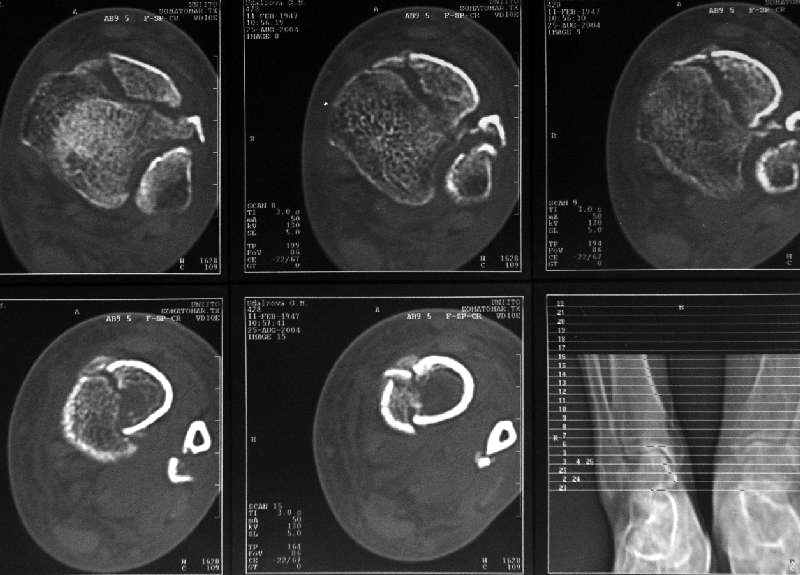

Дама 56 лет 6 недель назад получила спиральные переломы дистальных отделов костей голени. По месту жительства наложили гипс.

Сейчас вот, получается, спохватились. Снимки и КТ в приложении. Какой вариант тут предпочтительнее - открытая мобилизация, репозиция и внутренняя или наружная фиксация? Или ограничиться только резекцией костного шипа над шейкой тарана?Заранее спасибо.A female 56 y.o. 6 weeks ago sustained a fracture of the distal tibia/fibula. At the initial hospital a plaster cast was applied. Now she was referred to our unit. At the moment there is no pain, no obvious mobility. Images and CT attached.What is the best option here? Mobilize the fracture, perform open reduction and internal or external fixation? Or just to cut the anterior spike over the talar neck? THX in advance.

The anterior spike seems to be more antero-lateral, rather than anterior, in such a position that it may not hamper dorsiflexion.

The ankle mortise as a unit is intact.

Ребятки! 6недель-нет сращения-КТ подтверждает! Лечение 3 мира оставьте для третьего мира - у вас не составит особого труда разделить фиброзную ткань и сделать анатомическую редукцию.Фиксация-чем б-г пошлёт.

Здесь повреждение не диафизарное, смотрели состояние суставного конца кости и взаимоотношения таранной кости с этим шипом. Результаты КТ как раз повлияли на план, без нее пошли бы латеральным доступом, а после - передне-медиальным.